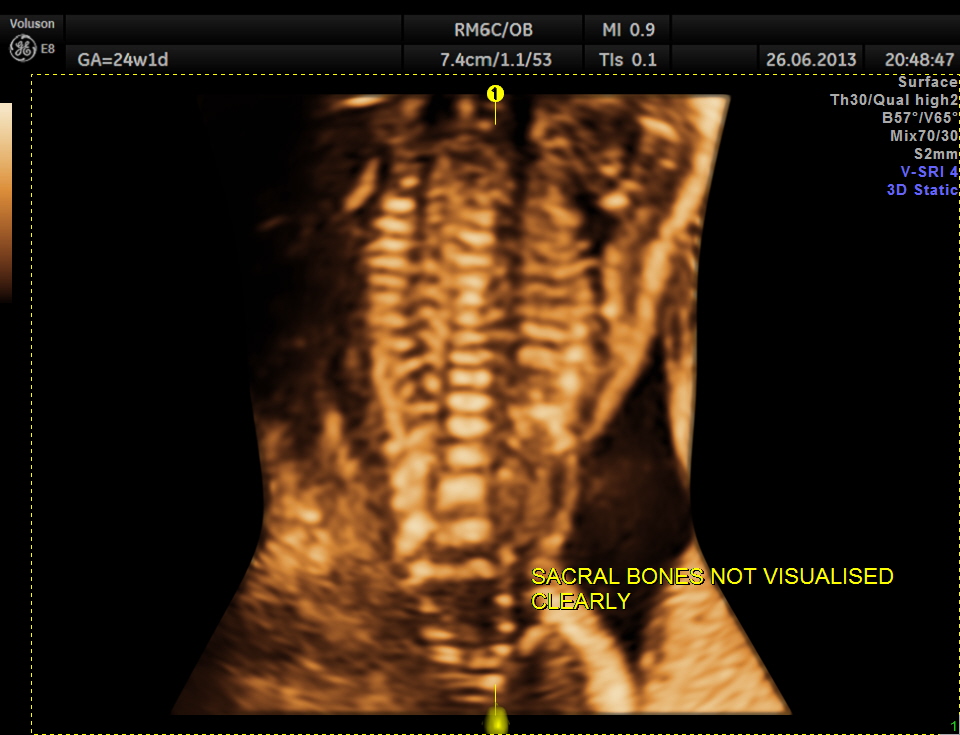

the next is a 3 d image of the open neural tube defect in the thoracic region

the following images are reconstructed images.